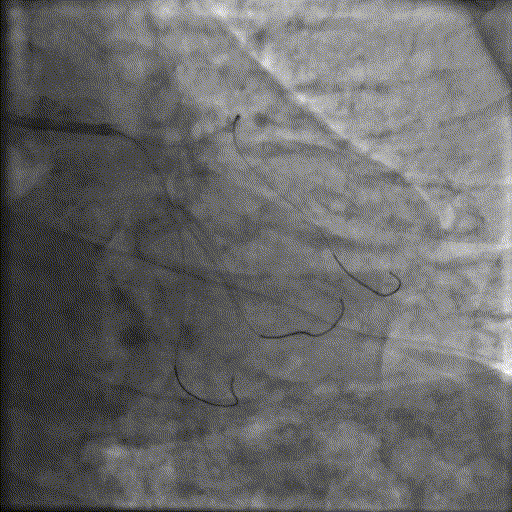

术前腔内影像学IVUS指导

IVUS提示血管内钙化严重,最小管腔面积不足 4mm²;遂考虑启动IVL治疗。

冲击波球囊治疗

2.5*12mm@4atm 冠脉血管内冲击波导管反复进行8个周期治疗,经IVUS检查提示最小管腔面积增加至4.88mm²;随后选取后扩张球囊对病变行扩张治疗。